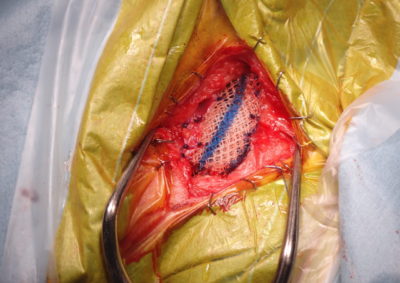

会陰ヘルニア